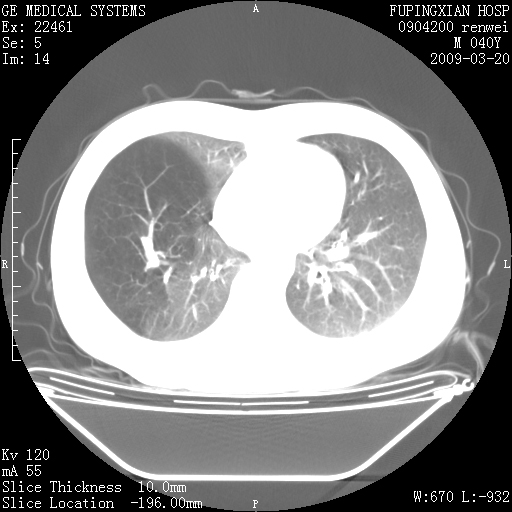

标题: CT18920:平时体健,体检时发现以下问题。 [打印本页]

标题: CT18920:平时体健,体检时发现以下问题。

单侧肺气肿表现,原因?   特发性或先天性可能

右肺气肿。

右肺局限性肺气肿

右肺局限性肺气肿。

右肺局限性肺气肿,有无呛咳史?

双肺弥漫磨玻样改变,肺纹理增重,考虑早期间质纤维化伴局部阻塞肺气肿,[考虑黏液栓]

右肺局限性肺气肿;[考虑黏液栓]所致。

双肺弥漫磨玻样改变,右肺局限性肺气肿。病人没有症状?

考虑间质性肺炎伴右侧局限性肺气肿,

先天性支气管闭锁

右肺局限性肺气肿,原因?先天支气管闭锁?粘液栓?